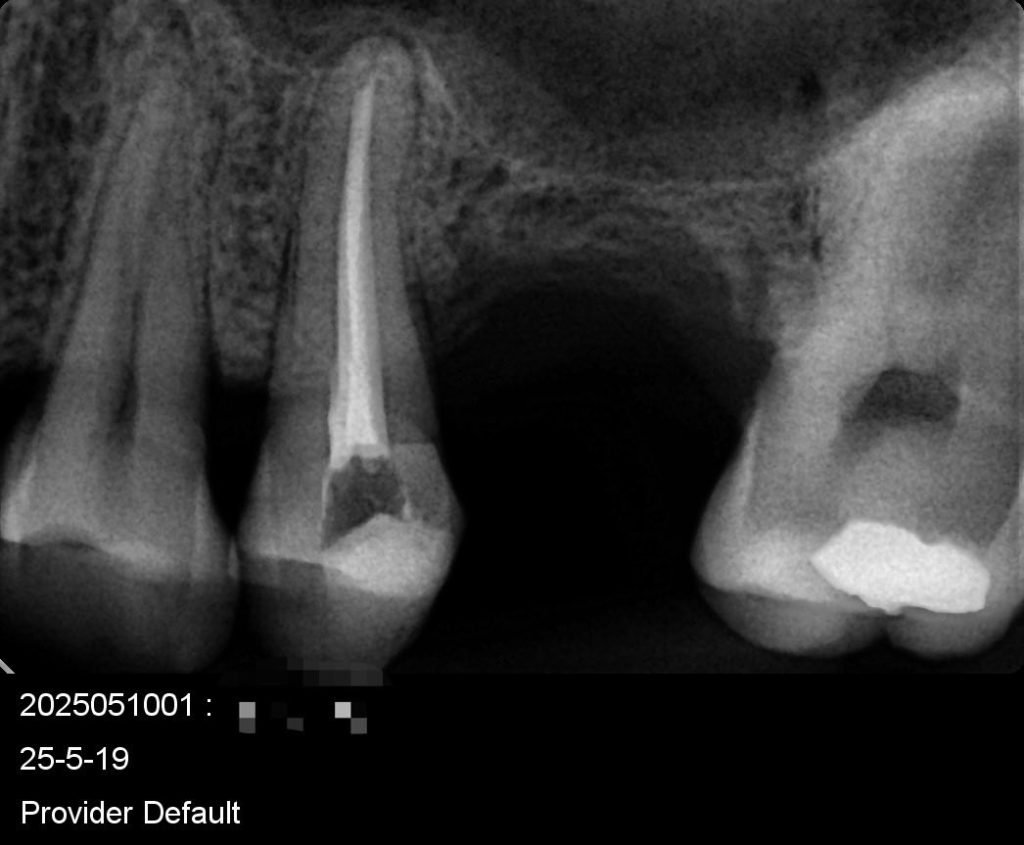

Caso de endodoncia Apertura pequeña

El uso de un cabezal de un contra Angulo en endodoncia , no puede dar ganancia en milímetros para poder instrumentar cómodamente y asi evitar fracturas o perforación al momento de instrumentar.